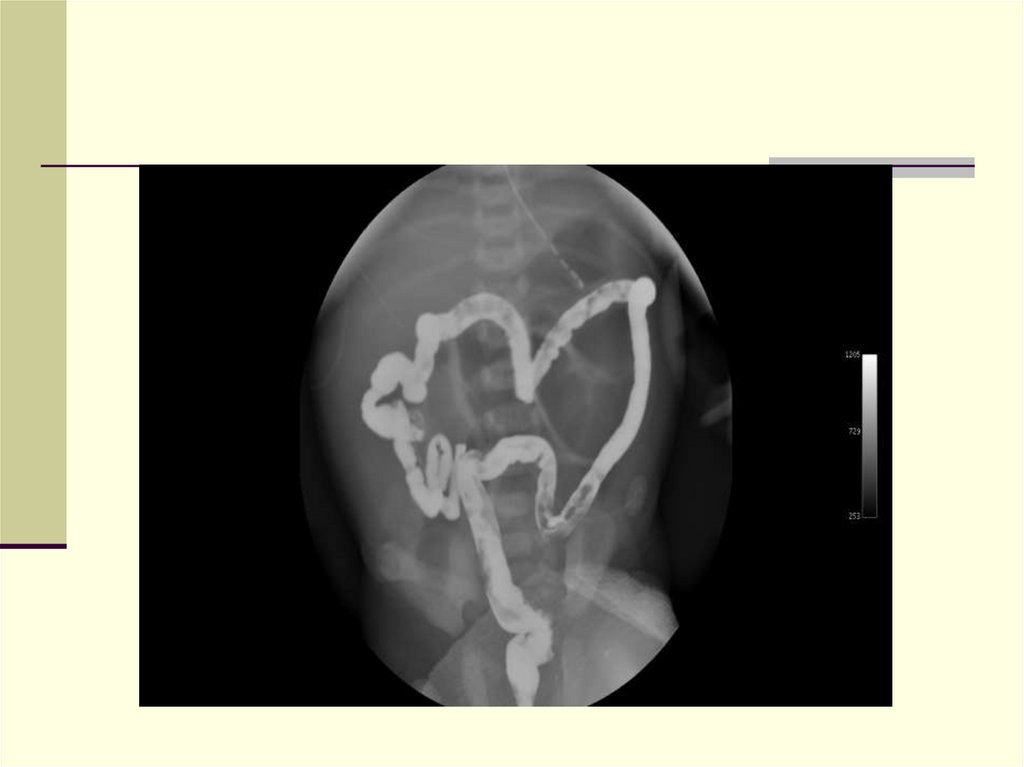

26. Диагноз

Обзорная рентгенография

Несколько расширенных петель с округлыми

образованиями в просвете

Отсутствие уровней

Кальцинаты в брюшной полости

Ирригография

Микроколон